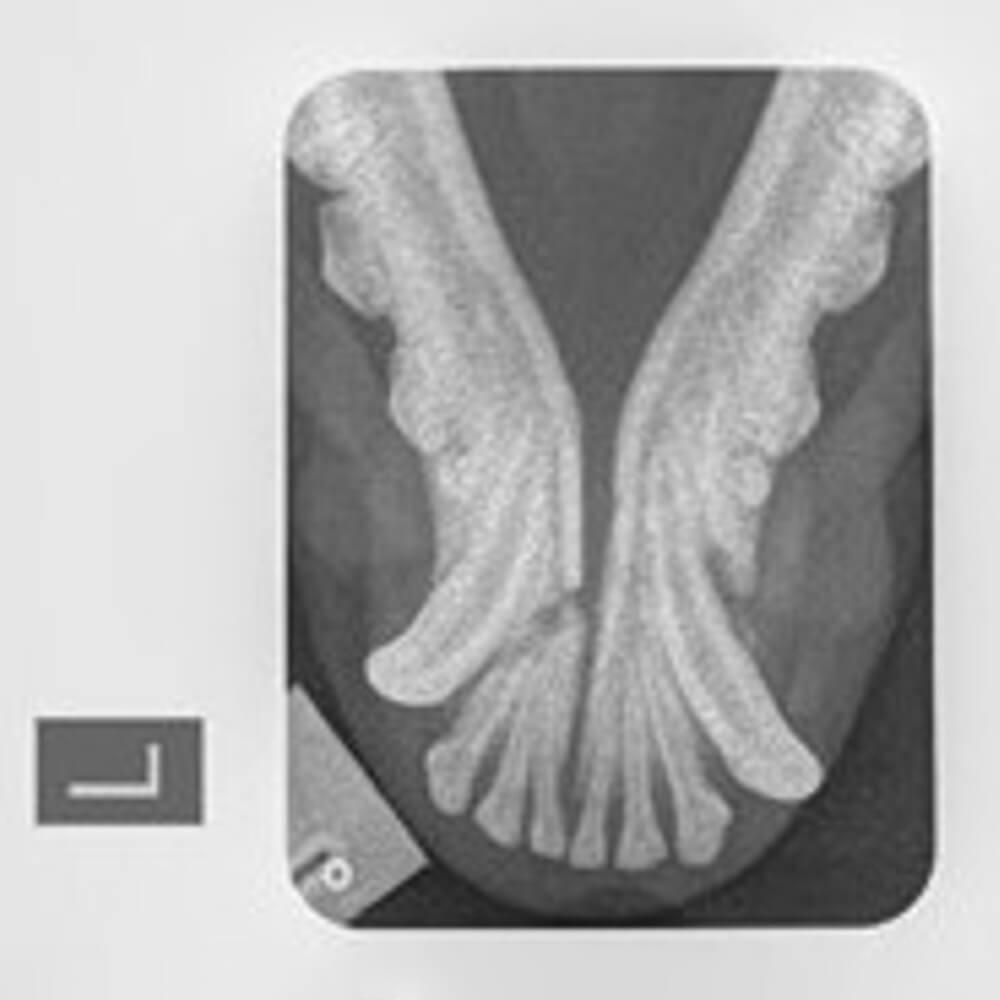

Under sedation radiographs were taken. Maya had fractured her jaw in two places which would require orthopaedic surgery to stabilise. Fortunately her lameness was only bruising and no other injuries were found.

Surgery stabilised the fracture with a combination of a bilateral external skeletal fixator and also an encircling wire. Maya went home with ‘bumpers’ on for two months to allow the bones to heal. The implants were removed at a second surgery. Maya has since made a full recovery, is always happy to see us, and continues to be her normal bouncy self!